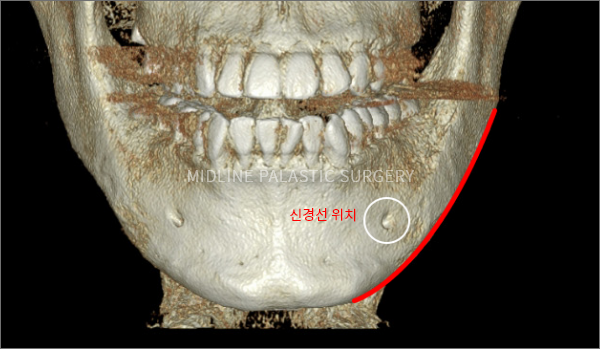

사각턱축소술

뼈의 절단면 비교

MIDLINE PLASTIC SURGERY

일반 사각턱수술

직선형태로 절골하여

이차각이 발생하여 부자연스러운 라인

올라운드 사각턱수술

한 번에 최대 길이의 곡선 형태로 절골하여

곡선의 형태로 자연스러운 라인